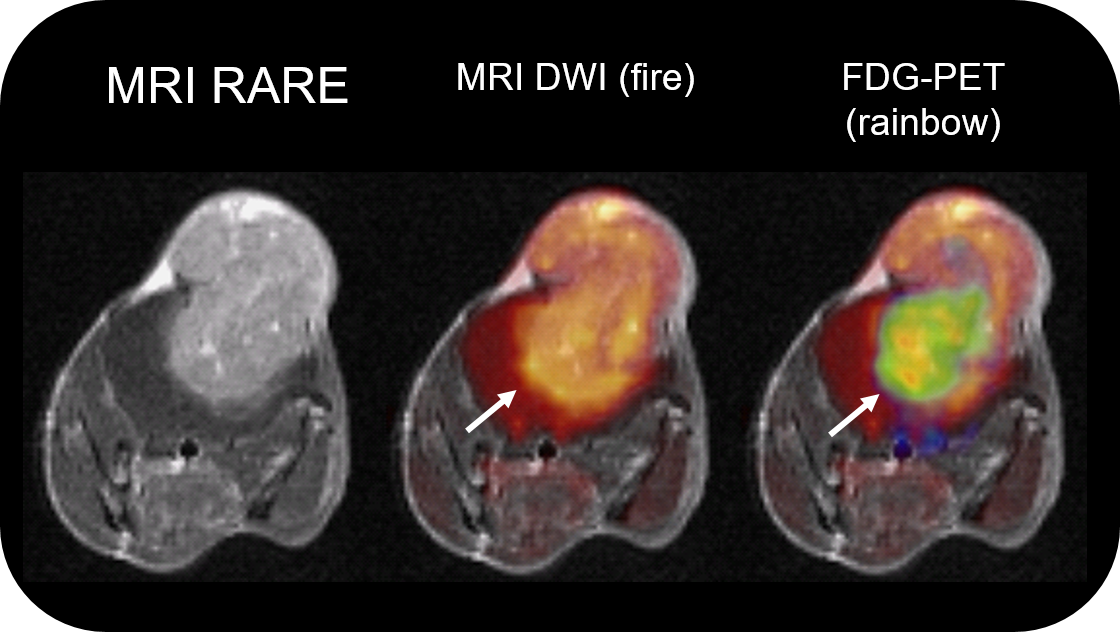

PET Insert or Inline

Upgradable with state-of-the-art PET module as inline or insert with full field of view and accuracy offers real, homogeneous sub-millimetric volumetric PET resolution and quantification in all three axes, in the entire field of view. This is possible due continuous crystal detectors with SiPM technology and true depth of interaction 3D precision equivalent to 10+ layer pixelated crystal detectors.

• Intuitive software package, for multi-dimensional MRI/MRS data acquisition, visualization, reconstruction, and analysis of MRI and/or PET/MR data